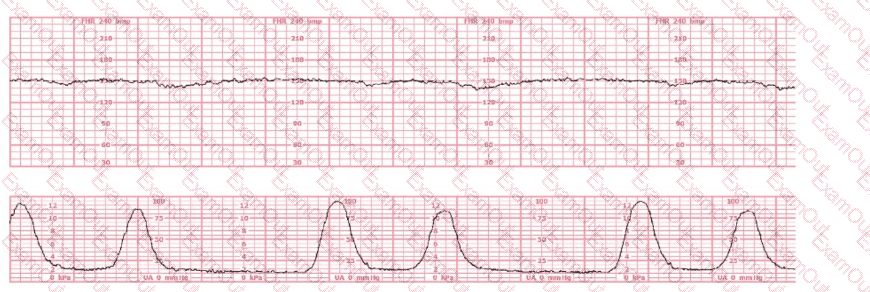

Uterine Activity:

The tracing shows very frequent contractions—approximately every 1½ to 2 minutes, which meets the NCC definition of tachysystole when averaged over 10 minutes (more than 5 contractions in 10 minutes).

According to NCC and AWHONN standards, when tachysystole is present with minimal variability, oxytocin must be reduced or discontinued even in the absence of late decelerations.

Clinical decision-making (per NCC principles):

NCC emphasizes that management of Category II patterns during induction starts with intrauterine resuscitative measures, including decreasing or stopping oxytocin when uterine activity is excessive or fetal response is suboptimal. Minimal variability with tachysystole requires correction of uterine stimulation before escalating to invasive monitoring or considering operative birth.

Option A (discontinue oxytocin) is the correct first-line action according to NCC-aligned guidelines when tachysystole and minimal variability occur.